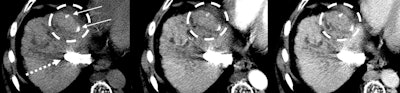

Images in a 55-year-old patient show hepatitis C-related cirrhosis and a transjugular intrahepatic portosystemic shunt (dashed arrow), with an undiagnosed tumor (dashed circle) at pretransplant imaging by both readers. Left: Noncontrast-enhanced axial CT image with a treated observation (dashed circles on the left, middle, and right images) and dense lipiodol staining (arrows) in the anterior right liver. Middle: Late arterial phase CT image with no appreciable enhancement. Right: Delayed phase image with no appreciable washout. The lesion was deemed at explant pathology to have 20% necrosis. Image courtesy of RSNA.